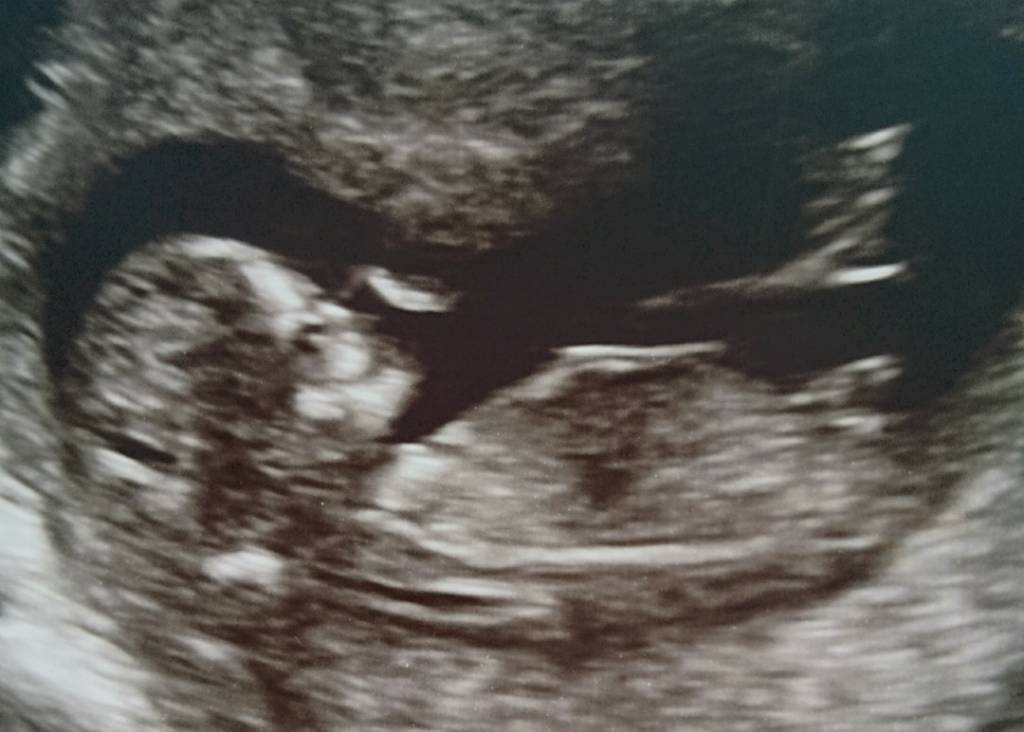

Tech was leaning pink... Thoughts???? Attachment 37718Attachment 37719

If what I'm seeing is the nub, I think boy. It looks really angled up.

I think I'd have to go boy [emoji170]on this one too